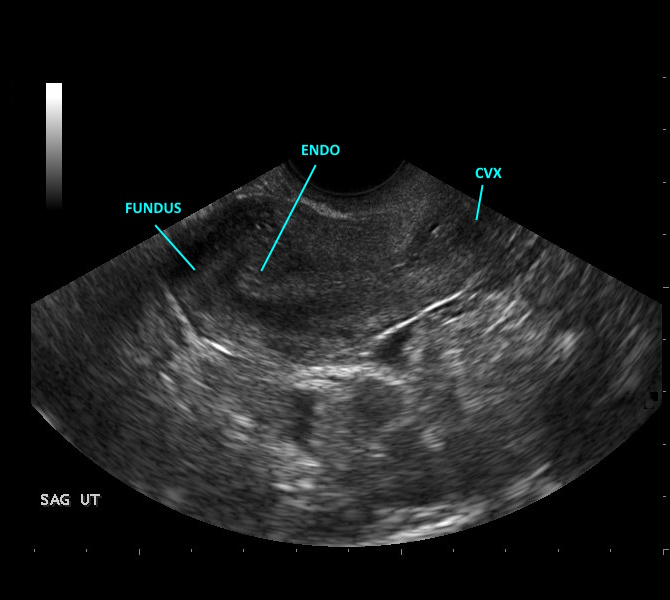

View-by-view acquisition guidance for pelvic and gynecologic ultrasound, aligned with current AIUM guidelines. Guides transabdominal and transvaginal technique with image optimization tips and normal measurement criteria for uterine and adnexal evaluation.